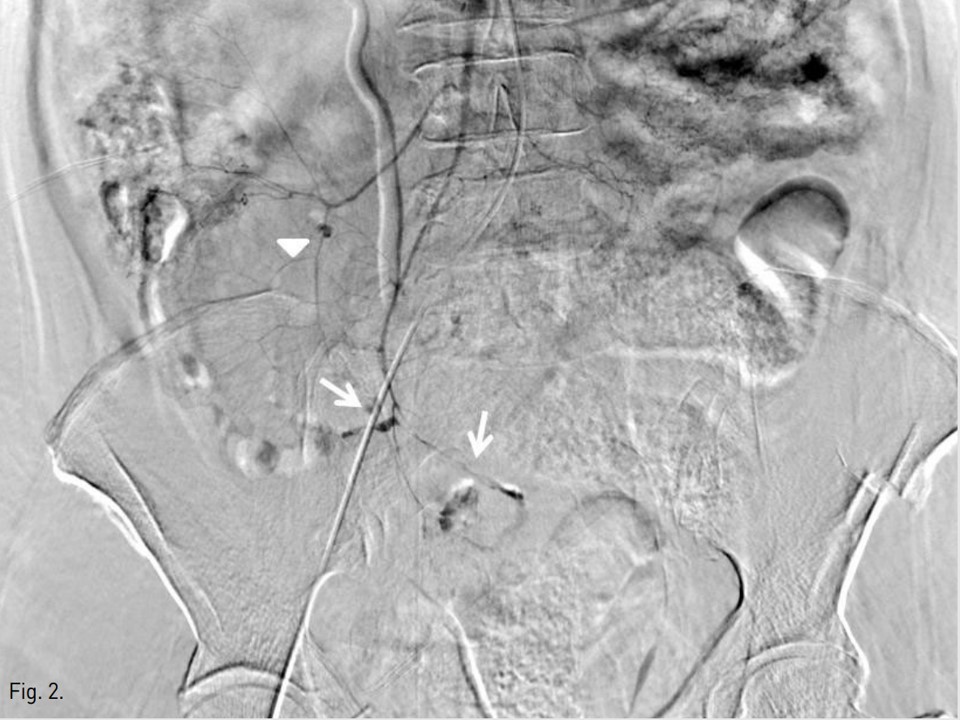

Fig. 3. B

Fig. 3A, B. Ileocolic (A) and right colic (B) arterial branches were embolized by using gelatin sponge, respectively(arrows).